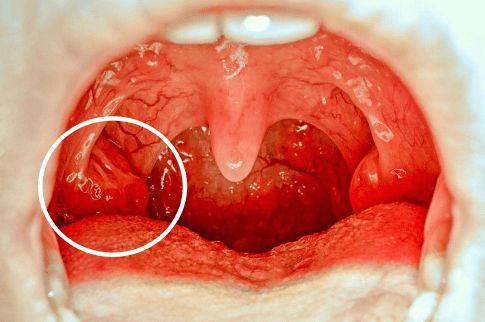

扁桃体窝白色东西图片

扁桃体窝白色东西图片,扁桃体白斑图片

小儿扁桃体上有「脓」,就是化脓性扁桃体炎吗?

扁桃体白斑图片

扁桃体角化症图片

扁桃体隐窝溃疡图片

扁桃体上白色隐窝图片

扁桃体隐窝白点图片